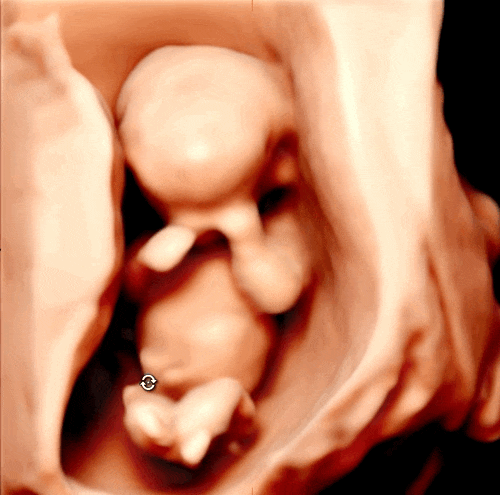

2024. 09. 13 (금) 8시 30분 채혈 9시 진료 예약 9시 05분 초음파실 진료 10시 교수님 진료 드디어 기다리...